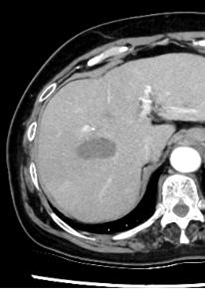

中央の肝臓がんの部分のみを焼灼